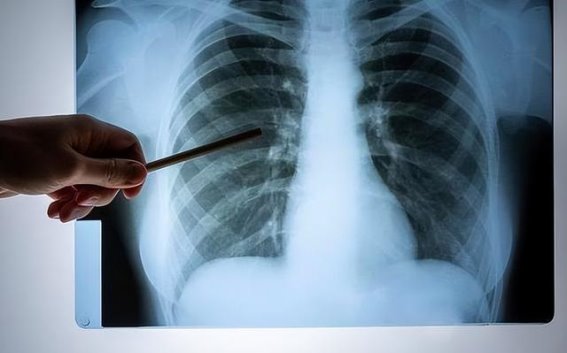

何时该警觉,如何应对?

并不是所有口腔异常都意味着肺癌。许多常见的口腔问题,如口腔炎、牙周病等,并不一定与癌症有关。但如果口腔问题持续时间较长,尤其是伴随其他肺癌相关症状,应该尽早就医。尤其是长期吸烟、有肺癌家族史的人群,更应定期进行肺部检查。

如果你长期口臭、咳血、口腔溃疡、牙龈出血、口干舌燥、味觉异常等症状,尤其是症状持续两周以上没有缓解,建议及时就医检查,进行肺部低剂量螺旋CT等基础筛查。